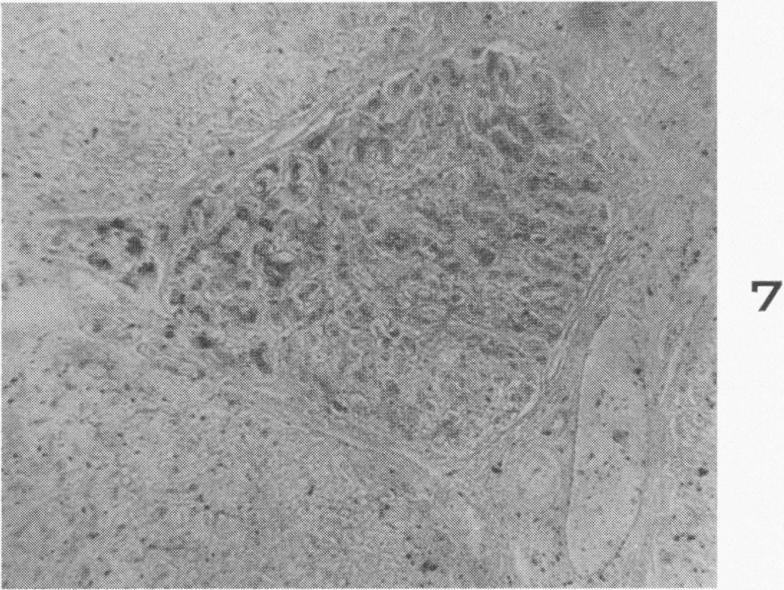

Histochemical demonstration of copper in a case of hepatolenticular degeneration.

Am J Pathol. 1955 May-Jun;31(3):545-53.

Histochemical demonstration of copper in a case of hepatolenticular degeneration.肝豆状核变性病例中铜的组织化学显示